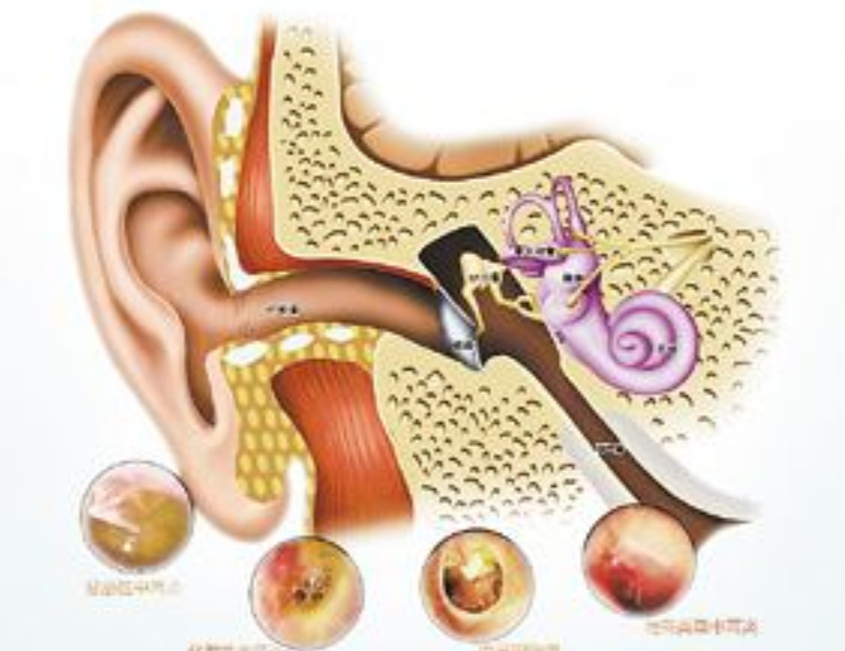

中耳炎圖片

什麼是急性中耳炎

A:中耳炎可能會引起患者出現多種耳部,以及全身的相關症狀,中耳炎的類型不同,所導致的症狀表現也會有所差異。對於常見的急性中耳炎情況,患者會出現突然發作的較為劇烈的耳痛症狀,也可能會同時伴有發熱、頭痛等症狀。部分患者會進一步導致中耳急性化膿性感……